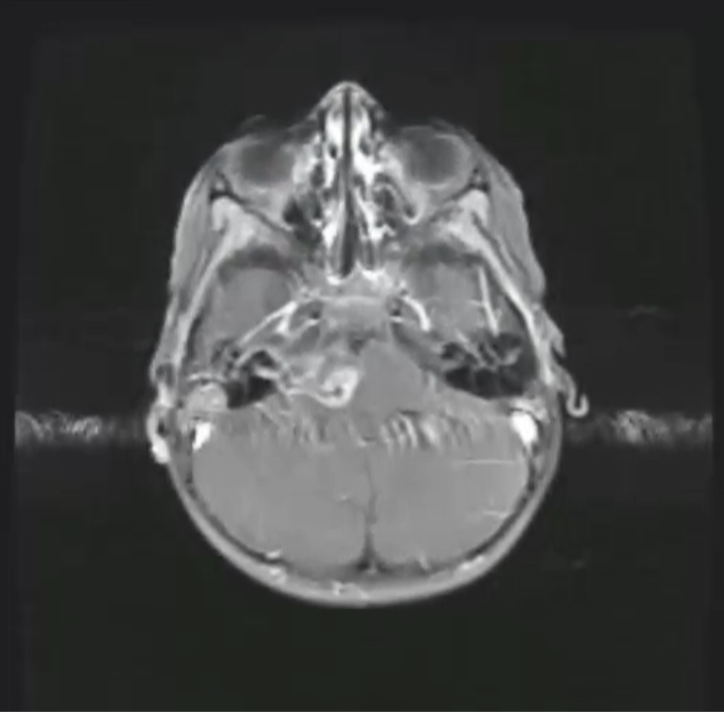

How can Gibbs artifact be minimized

Truncation errors (Gibbs artifact) can be minimized by increasing the number of phase-encode steps or by reducing the field of view.

What was the most likely step taken to eliminate the artifact seen in the first image?

Increasing the matrix size decreased truncation artifact (aka Gibbs, or ringing).

choosing a smaller FOV can also help eliminate this artifact